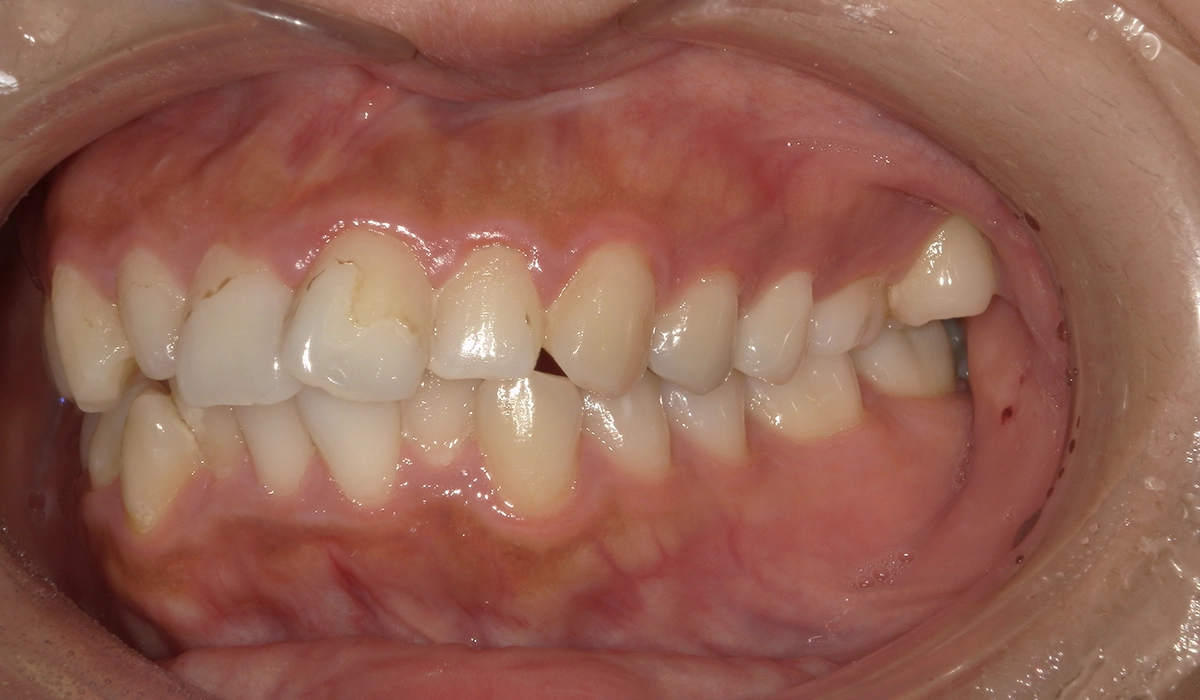

今回ご紹介する患者様は、上下の歯並びのガタツキを気にされており、矯正検査後叢生Ⅱ級と診断いたしました。

術前:正面

| 主訴 | 上下の歯並びのガタツキが気になる |

| 治療期間 | 20カ月 |

| 治療費用 | 660,000円(税込) |

| 治療内容 | 上下の歯並びのガタツキを気にされており、矯正検査後叢生Ⅱ級と診断いたしました。 |